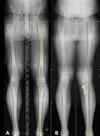

A 40-year-old man who is a manual laborer has had 3 years of worsening medial-sided left knee pain that has inhibited his ability to work. He reports undergoing a left subtotal medial menisectomy 10 years ago. He has been treated with nonsteroidal anti-inflammatory drugs and 2 different corticosteroids, with the most recent injection given 1 month ago. Each injection provided him with a few weeks of pain control. His medical history is unremarkable and he has smoked 20 cigarettes per day for the last 15 years. His body mass index (BMI) is 22. On examination, he has varus alignment of the involved leg and medial joint line tenderness and no lateral or patellofemoral pain. His knee range of motion is 3° shy of full extension to 130° of flexion. He has negative Lachman and posterior drawer test results. He demonstrates no lateral thrust with ambulation. What imaging study is most appropriate to determine treatment options for this patient? Based on his exam, what should be the next step in management after imaging?

This patient has a classic presentation of postmeniscectomy medial compartment arthritis. The appropriate diagnostic study is weight-bearing radiographs to confirm the diagnosis. An MRI scan will reveal medial compartment arthritis but will not provide information about alignment. A CT scan would be appropriate to detect an occult fracture; however, this condition is not suspected in this clinical scenario. Ultrasonography can provide information about fluid collection around the knee or a deep vein thrombosis; however, these conditions also are not suspected in this clinical scenario. Because the patient has a correctable deformity (gaps 3 mm with valgus stress), and his symptoms are localized to the involved compartment, a trial of a medial unloader brace is appropriate both diagnostically and therapeutically. If unloading the medial compartment resolves the patient's symptoms, he would be an excellent candidate for an osteotomy. An MRI scan may be obtained to evaluate ligamentous integrity or to evaluate degenerative involvement of the lateral and patellofemoral compartment for presurgical planning of an osteotomy; however, the integrity of the medial meniscus has no clinical importance in a patient with severe medial compartment arthritis. A repeat corticosteroid injection is not indicated within 1 month of his last injection, and referral to pain management is not appropriate with other options available to help this patient. A VPHTO is the appropriate intervention considering the patient's young age, high-functional occupation, examination, radiographic findings, and response to medial unloader bracing. A revision knee arthroscopy would be appropriate for a recurrent medial meniscus tear, but not appropriate in a patient with severe medial compartment arthritis. The patient's young age and high functional requirements are contraindications to TKA. The presence of severe arthritis is a contraindication to medial meniscus transplant. The patient is a candidate for a VPHTO. The technical options include a medial opening-wedge or a lateral closing-wedge osteotomy. Both techniques have advantages and disadvantages; however, a medial opening-wedge osteotomy is contraindicated in a smoker because of concern for nonunion. As a result, current smoking history is the only factor listed that would influence the technique used. The history of prior arthroscopy has no relevance in the decision about which type of osteotomy is appropriate. Normal BMI is between 18.5 and 24.9, so this patient's BMI is considered normal and would not affect the surgical technique (if this patient were obese, a lateral closing-wedge osteotomy would be considered, but this is controversial). His age of 40 years is an indication for HTO but does not influence technique.